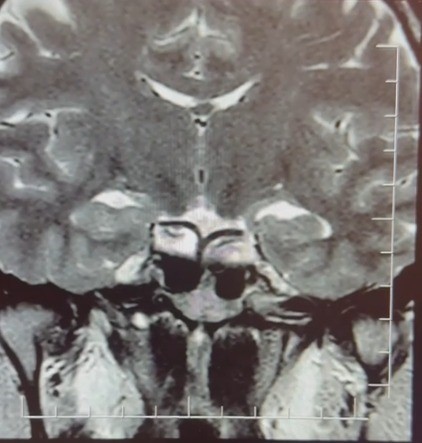

Yapılan ileri tetkiklerde hastaya hipofiz MR çekildiğini aktaran Çiftçoğlu, “MR sonucunda beynin hipofiz bölgesinde ‘prolaktinoma’ olarak adlandırılan bir tümör tespit ettik. Bu tümör, prolaktin hormonunun aşırı salgılanmasına neden oluyor. Genellikle iyi huylu olup ilaç tedavisiyle kontrol altına alınabiliyor” diye konuştu.

Gebelik belirtilerine benzer şikayetlerin farklı hastalıkların habercisi olabileceğine dikkat çeken Çiftçoğlu, “Prolaktin hormonu aslında beyinde hipofiz bezinden salgılanan ve süt salınımını sağlayan hormondur. Bunun yüksek olduğunu tespit ettikten sonra hastada hipofiz MR çektirdik. Çektiğimiz beyin MR’ında hastanın hipofiz dediğimiz bölgede kitleyi tümörü tespit ettik. Prolaktinoma dediğimiz bir tümör. Prolaktinoma tümörü beyinde hipofiz bölgesinde bulunmakta olup prolaktin hormonunun aşırı miktarda salgılanmasını sağlayan bir tümördür. Bu durumda iyi huyludur, kanserleşme olmasını çok yoktur. Dolayısıyla ilaçla tedavisi mümkündür ama gebelik şikayetlerini de andırdığı için mutlaka ayırıcı tanıda akılda tutulması gereken bir durumdur. Hasta da bizle öğrendi ’hamileyim’ diye geldi hasta, gebelik muayenesi olma talebiyle geldi ancak biz tümörü tespit ettik. Önce gebe olmadığını tespit ettik ve sonra ’Bu şikayetlere sebep olabilecek ne var?’ diye araştırdığımızda bu durum ortaya çıktı. Yani tümörü de aynı gün içerisinde değil birkaç gün sonra ileri tetkik sayesinde öğrenmiş oldu” dedi.